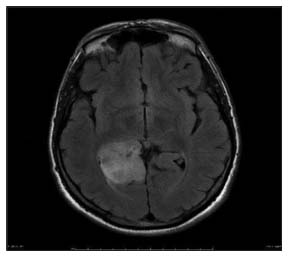

| Figure 1 Magnetic resonance imaging of glioblastoma multiforme